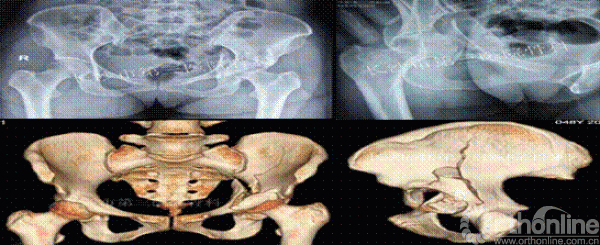

病史资料:患者女性,48岁,因外伤致左髋疼痛活动受限6日入院。6天前因高处坠落致左髋疼痛活动受限,由120急送入院。查生命体征平稳,左髋部略肿胀,左腹股沟广泛压痛,大转子处叩击痛,左下肢纵向叩击痛,左髋主动被动活动受限,左下肢末梢血运、感觉可,无神经功能受损表现。实验室检查(血常规、肝肾功能、血糖、凝血常规、输血前四项、血沉、C反应蛋白)正常,心电图正常。

术前影像

诊断:左髋臼粉碎性骨折。

髋臼粉碎性骨折的治疗,一直是骨科创伤治疗的一个难题,其原因是髋臼解剖形态不规则,而且位置较深,骨折碎片移位复杂,传统手术切口较大,手术中需要反复预弯柔性钢板,耗时较长,出血量增加,预弯过多可致金属疲劳内固定断裂风险增加,固定螺钉的型号及置钉方向的选择仅仅凭借X、CT片及术者的经验风险较大,易于损伤神经、血管、膀胱直肠等盆腔内重要脏器,3D打印模型的出现,使得上述问题可以较为直观的解决,对于手术路径的选择及细节问题的处理更加面面俱到,3D打印模型的出现,让医患之间的沟通变得更加简单直接,术者信心增加,因为手术切口的变小、手术时间的缩短、骨折块精确的复位,手术并发症相应减少,患者康复出院的时间缩短,使得患者直接受益,因此出现医患多赢的格局,值得推广。